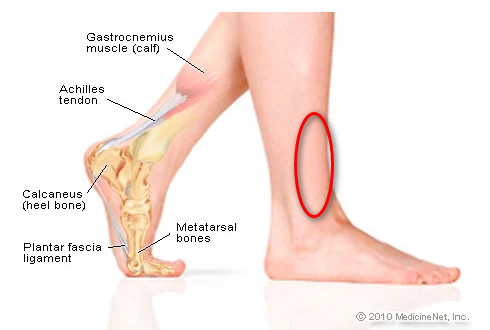

Возможные причины болей в ноге ниже колена и рекомендации